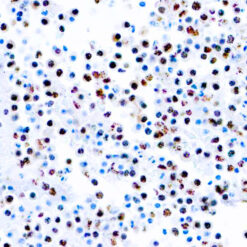

Solitary fibrous tumor (SFT) is a fibroblastic neoplasm of variable biologic potential that can arise at a wide range of anatomic sites. Almost all cases of (98%) including conventional, cellular, atypical, and malignant variants showed nuclear expression of STAT6. Staining for STAT6 was usually diffuse: 68% of cases showed reactivity for STAT6 in 75% of tumor cells. Further, the intensity of staining was strong in 67% of cases, moderate in 25%, and weak in only 7%. The heterogeneity of staining, both in terms of extent and intensity, which may be because of uneven tissue fixation or loss of antigenicity in older cases for which the unstained slides were stored for extended periods of time. All other tumor types examined were negative for STAT6, except for three dedifferentiated liposarcomas and one deep fibrous histiocytoma, which showed weak staining. STAT6 is therefore a highly sensitive and almost perfectly specific immunohistochemical marker for SFT, and can be helpful to distinguish this tumor type from histologic mimics.